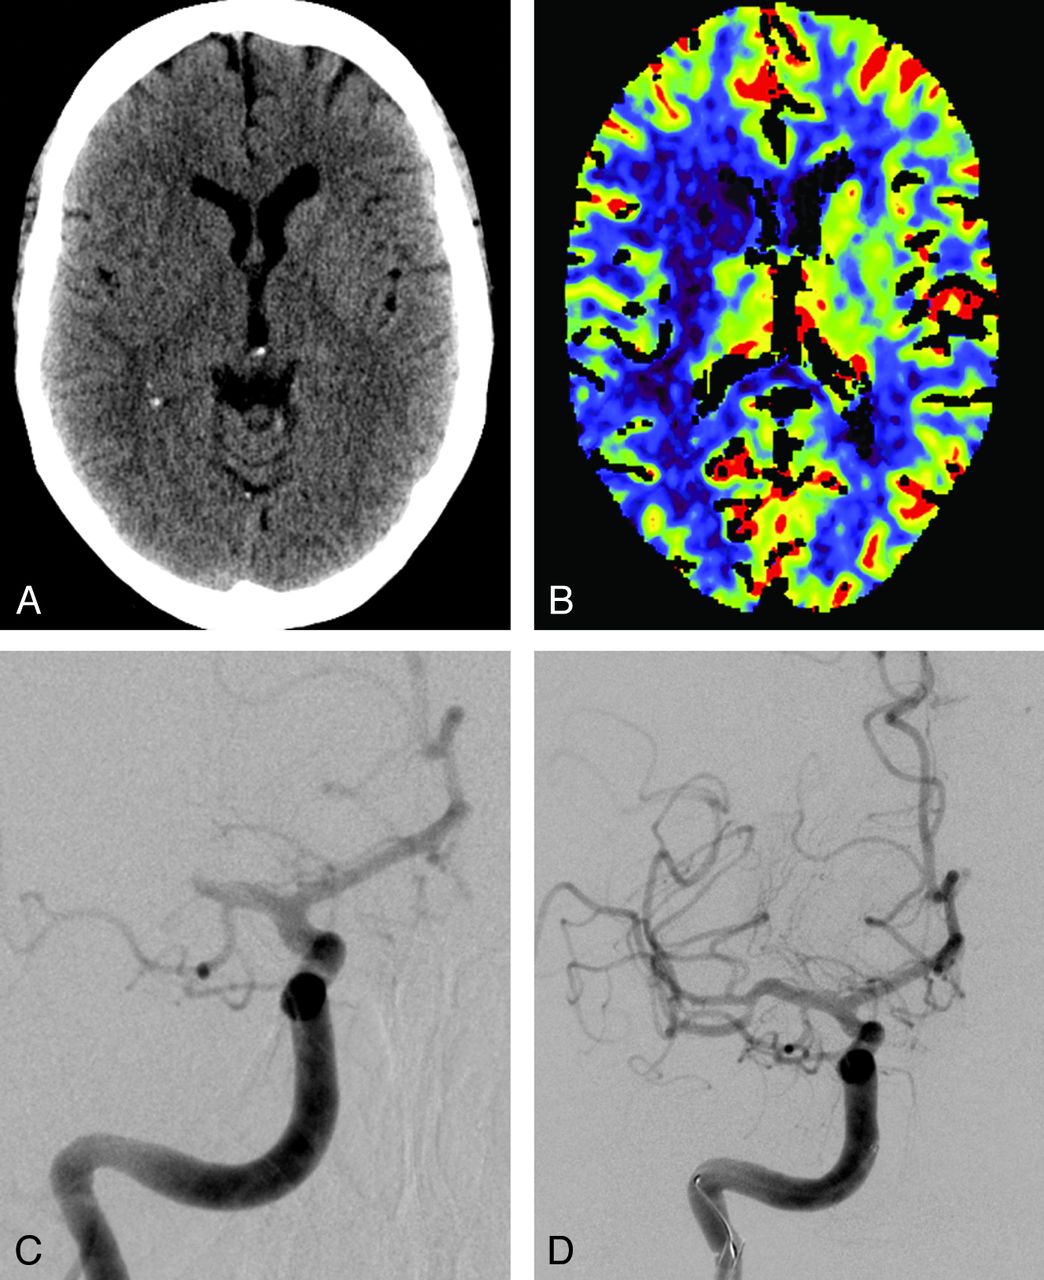

A 36-year-old woman with an acute left hemiparesis and an admission mRS of 5. A and B, Noncontrast CT scan shows subtle low attenuation in the right putamen and head of the caudate nucleus; CT perfusion shows a significant reduction of cerebral blood flow in the right MCA territory. C, After initiation of IV-rtPA, the patient was transferred to the angiography suite and a persistent occlusion (TICI 0) of the M1 segment of the right MCA is shown on the posteroanterior angiogram. D, Successful recanalization (TICI 3) was achieved after thrombus aspiration with the PS. Total time from symptom onset to successful recanalization was 205 minutes. The patient was discharged to the rehabilitation unit with an mRS score of 4 after 11 days, and a favorable outcome with an mRS score of 2 was diagnosed at follow-up.